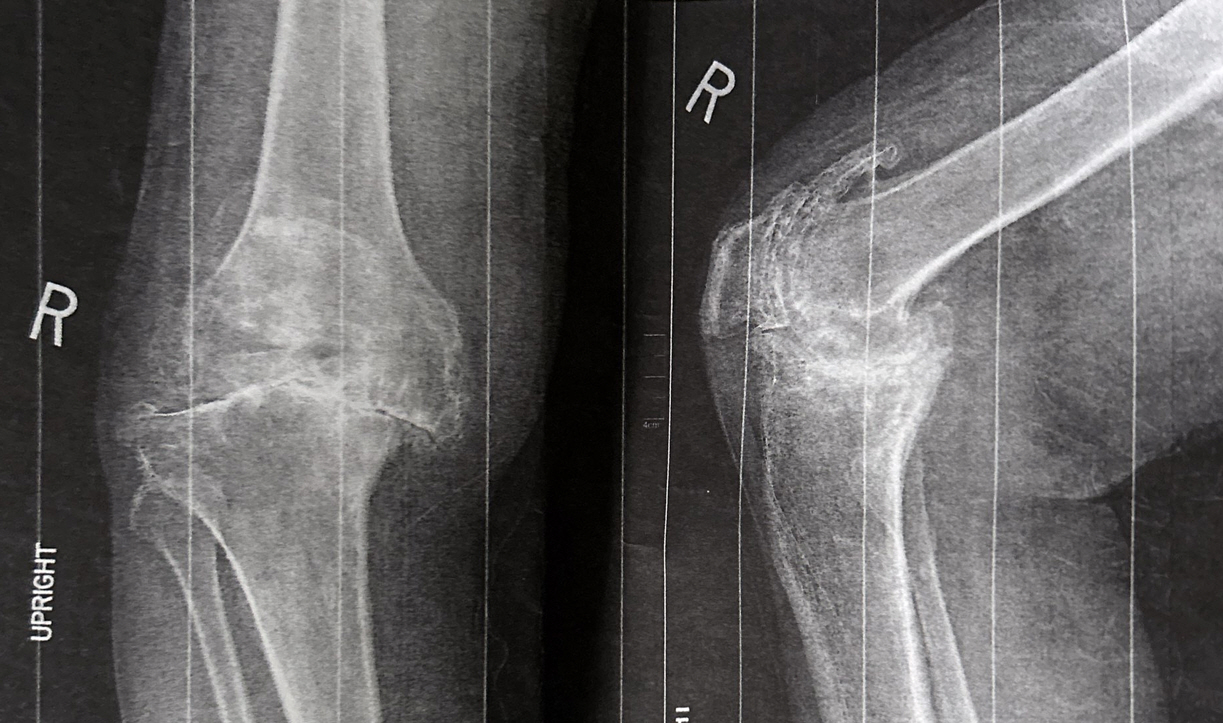

Sever DJD

5. Review of the most common disorders of the knee region (Iliotibial band Syndrome, Osgood-Schlatter disease, Baker Cyst, and Knee OA)

6. Total Knee Arthroplasty TKA, Pre and post-operative rehabilitation, Complications, and Causes of persistent pain and imping after TKA